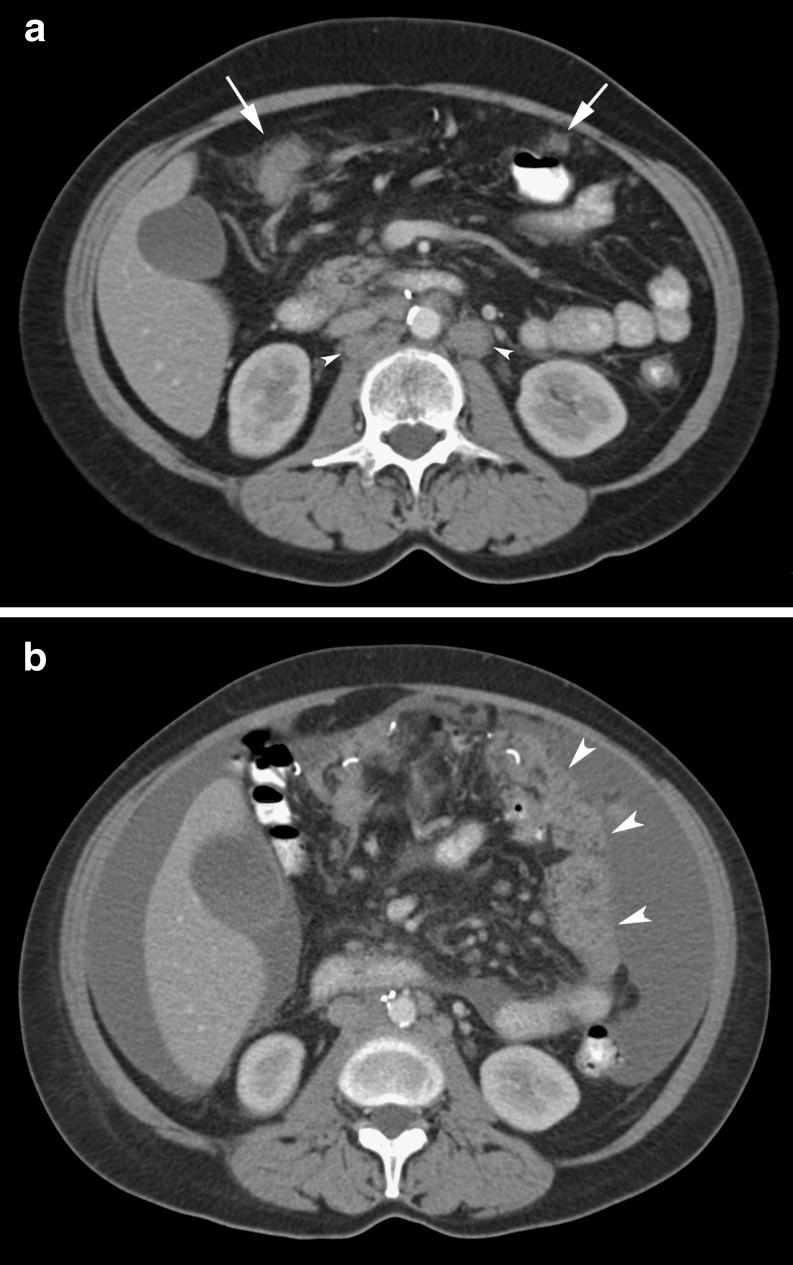

Omental cakes typically are associated with ovarian carcinoma, as this is the most common malignant aetiology. Nonetheless, numerous other neoplasms, as well as infectious and benign processes, can produce omental cakes. METHODS: A broader knowledge of the various causes of omental cakes is valuable diagnostically and to direct appropriate clinical management. RESULTS: We present a spectrum of both common and unusual aetiologies that demonstrate the variable computed tomographic appearances of omental cakes. CONCLUSION: The anatomy and embryology are discussed, as well as the importance of biopsy when the aetiology of omental cakes is uncertain.